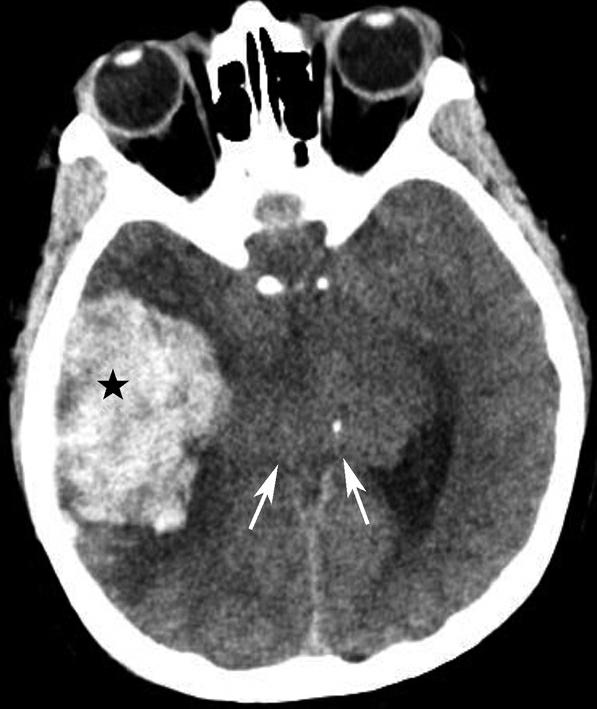

图1-2-20 环池闭塞

右侧颞叶脑内大血肿(★),产生严重的占位效应,环池受压闭塞(箭),脑疝形成